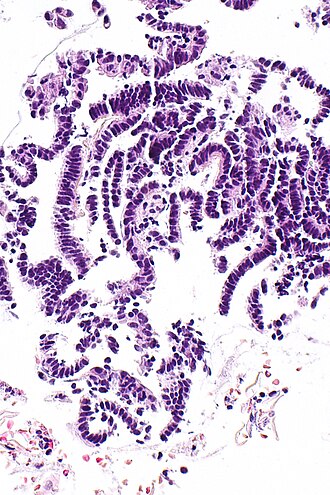

|

Inactive endometrial epithelium. H&E stain. | |

Features:

- Glands - small columnar cells:

- Moderate quantity of eosinophilic cytoplasm.

- Ovoid (palisaded) nuclei +/- nuclear pseudostratification.[2]

- Eosinophilic cytoplasm.

- No mitoses.

- Architecture:

- +/-Cystic dilation.

The sections show small fragments of endometrium. The gland-to-stroma ratio is normal. The glands are small and round, and have a pseudostratified epithelium.

Mitotic figures are not identified within the glands or stroma. No stromal condensation is apparent. No secretions are in the glands. No nuclear atypia is apparent.